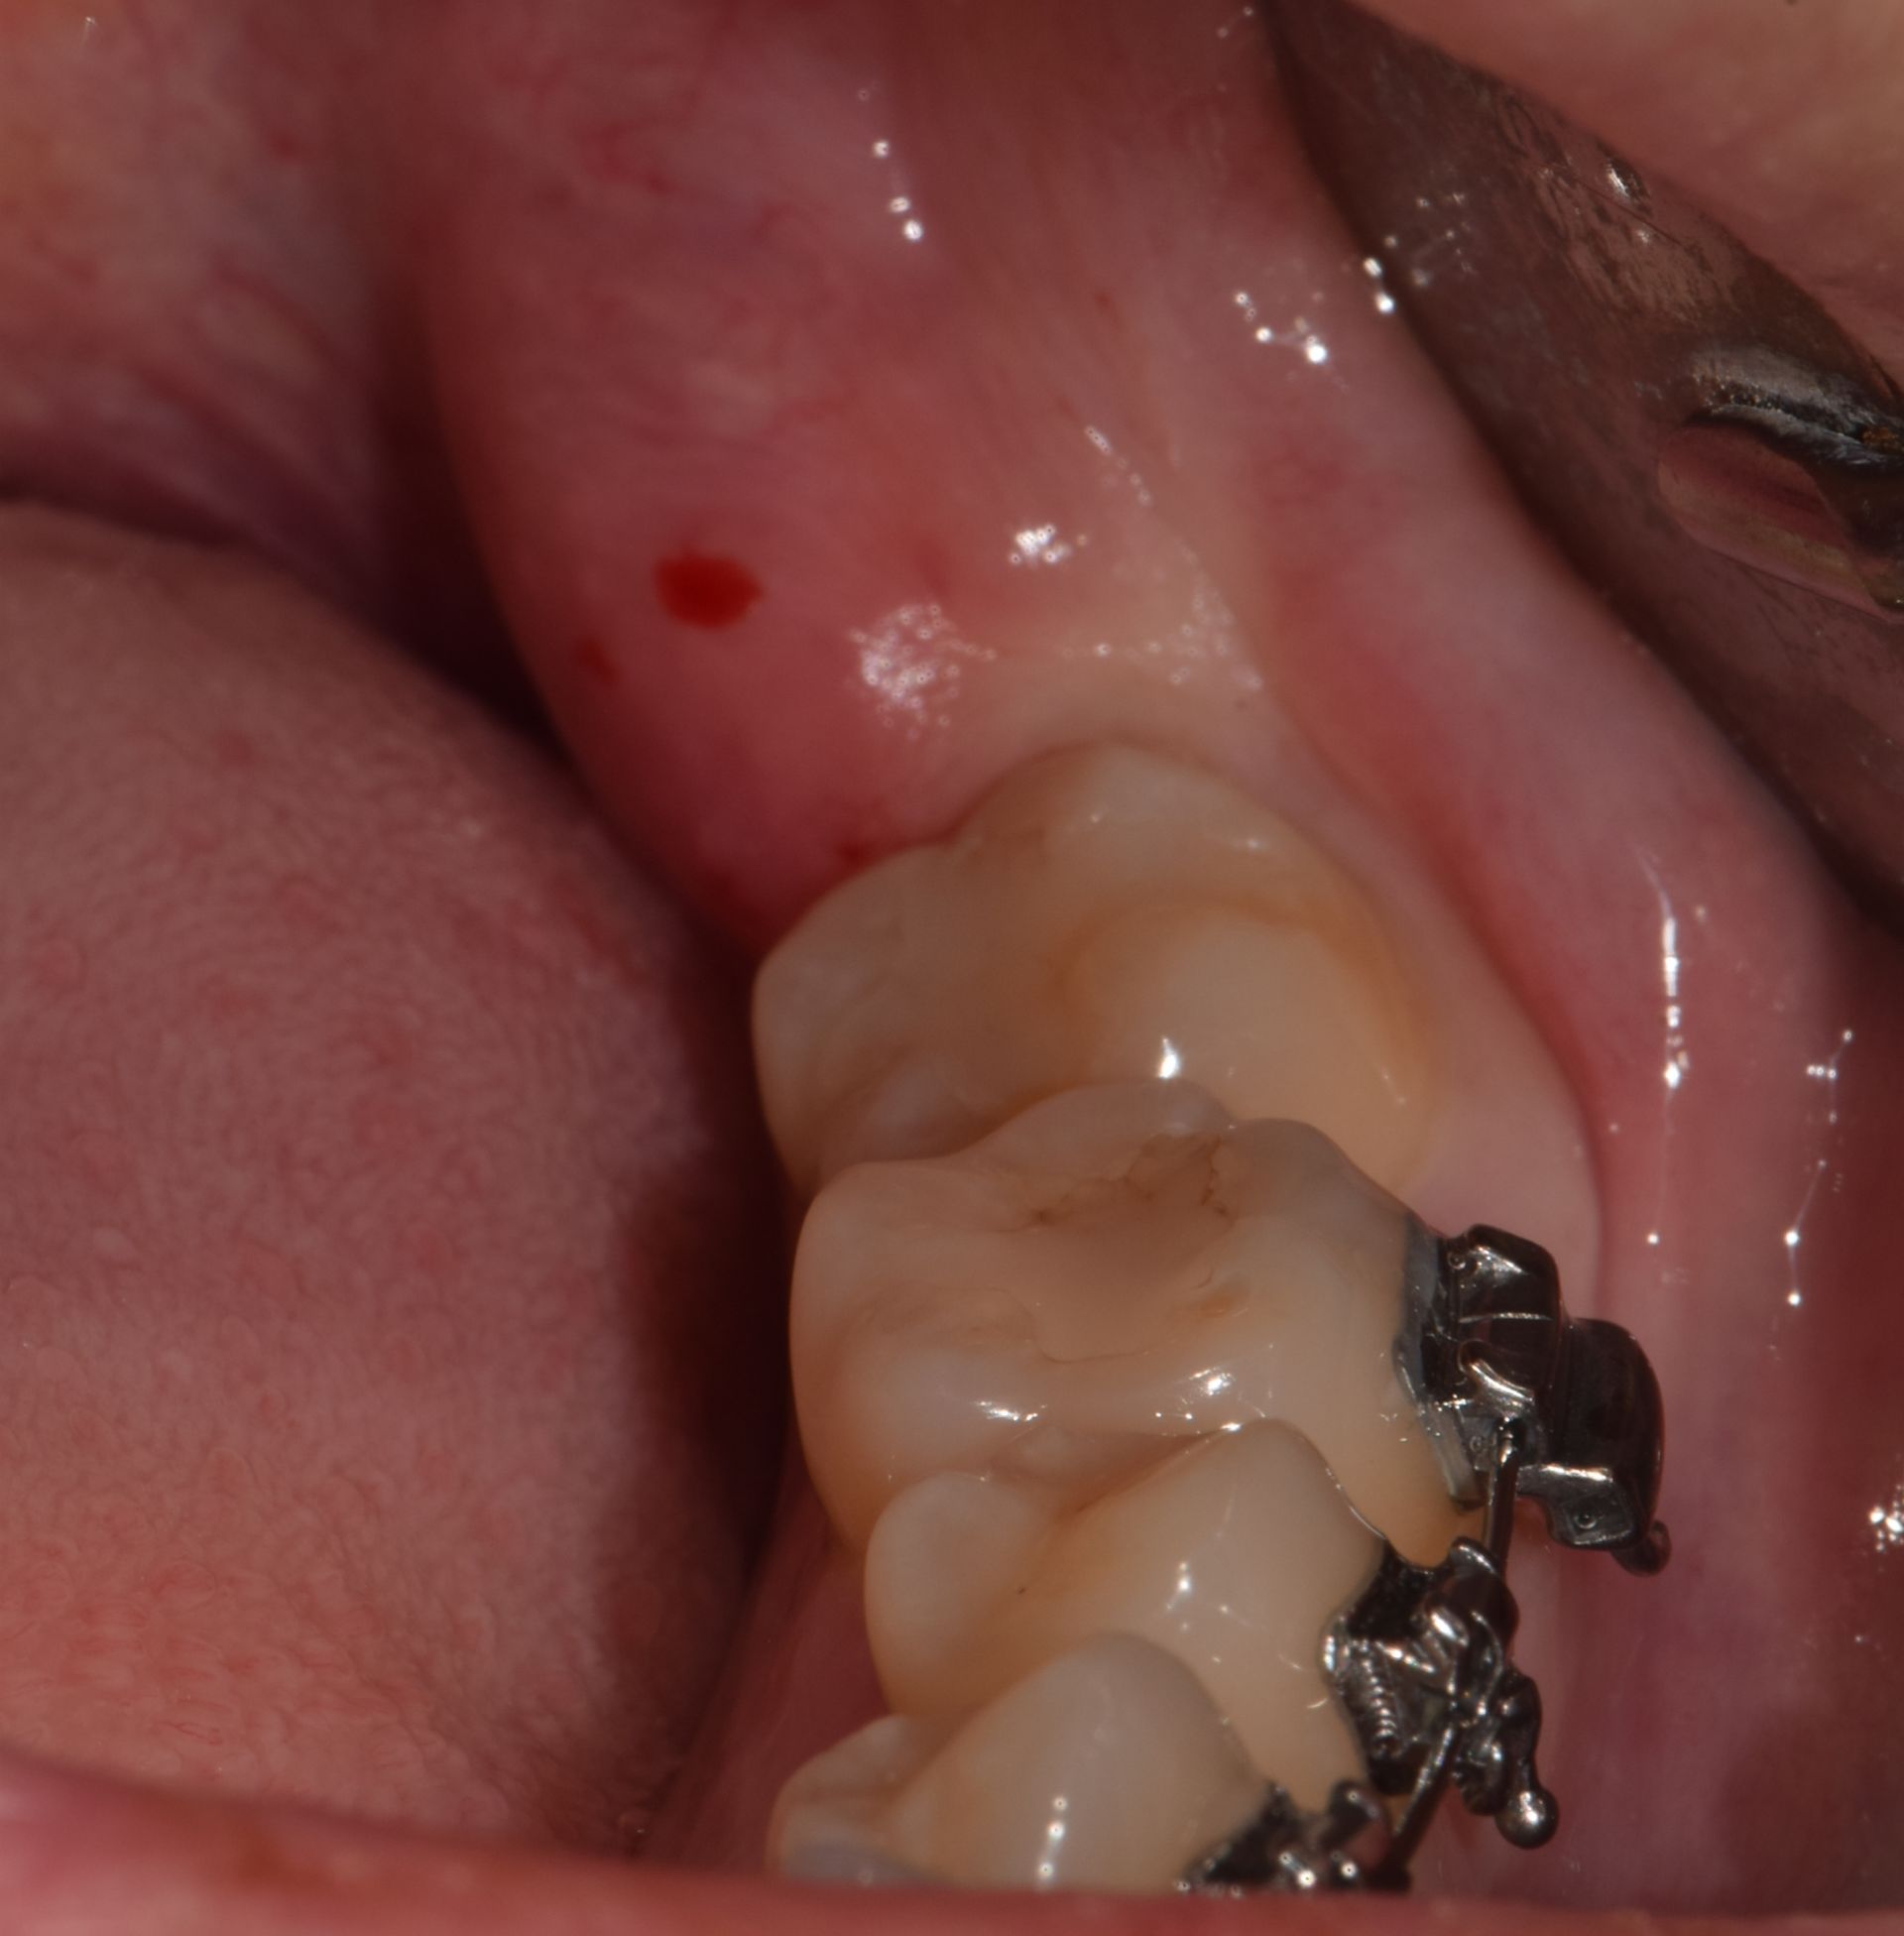

확장 개원 후, 첫 번째 사랑니 환자입니다. 잇몸 밖으로 보이지도 않고, 절개를 해도 뼈만 보이고 사랑니는 보이지를 않습니다. 이 정도면 사랑니 중에서도 난도가 높은 편입니다. 발치하는 데 얼마나 걸릴까요? 빨리 뽑는 것보다 잘 뽑는 게 중요하지만, 역설적으로 잘하는 의사는 빨리 뽑습니다. 그리고 약물 처방 외에도 주사 처방을 통해 붓기를 조절해 드립니다.

확장 개원 후, 첫 번째 사랑니 환자입니다. 잇몸 밖으로 보이지도 않고, 절개를 해도 뼈만 보이고 사랑니는 보이지를 않습니다.

이 정도면 사랑니 중에서도 난도가 높은 편입니다. 발치하는 데 얼마나 걸릴까요?

빨리 뽑는 것보다 잘 뽑는 게 중요하지만, 역설적으로 잘하는 의사는 빨리 뽑습니다. 그리고 약물 처방 외에도 주사 처방을 통해 붓기를 조절해 드립니다.